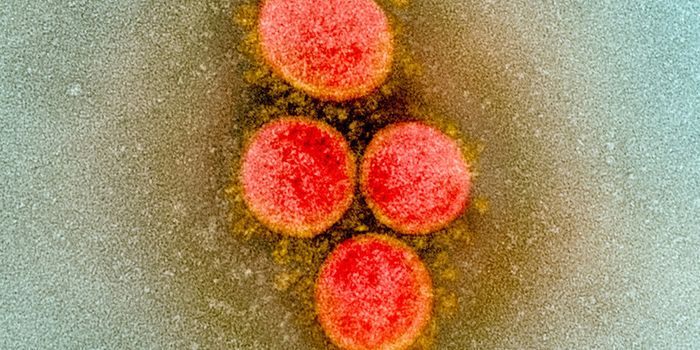

SEP 07, 2021MicrobiologyThe world has rapidly become familiar with sarbecoviruses, two of which jumped to humans in recent years. The first was ...

DEC 24, 2020MicrobiologyThe UK recently reported that it had detected a new variant of the SARS-CoV-2 pandemic virus, which causes COVID-19. Thi ...